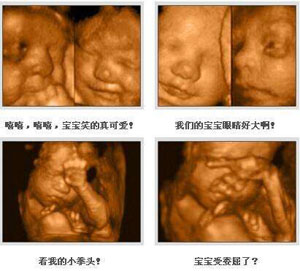

四维彩超表面成像用于产科检查,不仅可观察到胎儿成长的过程,而且能够直观地看到胎儿在母体内的活动状况,如:呼吸情况,运动情况,包括整个身体大的运动,肢体的运动,甚至是胎儿细小的吞咽动作等。

孕妈妈为了宝宝的健康,做4维彩超是很有必要的。四维彩超不仅可以做好产前的排畸检查,而且准妈妈还能和宝宝提前见面,观察到宝宝的可爱模样。